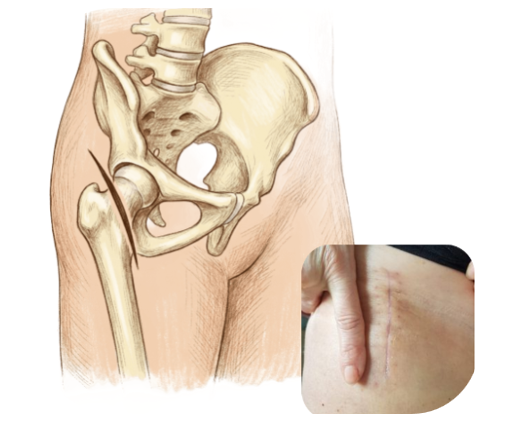

Tecnica mini-invasiva con accesso anteriore

L’intervento viene eseguito tramite accesso anteriore mini-invasivo, una tecnica che:

rispetta muscoli e tendini

riduce il sanguinamento

favorisce un recupero più rapido

✔ Recupero funzionale più rapido ✔ Minore dolore post-operatorio ✔ Cicatrice più contenuta ✔ Minore rischio di differenze di lunghezza degli arti ✔ Migliore ripresa della vita attiva